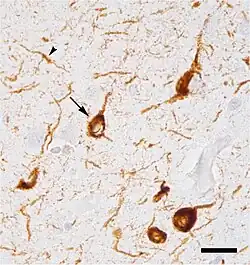

The main pathological characteristic of Parkinson's disease is cell death in the substantia nigra. In particular, this death occurs in the ventral part of the pars compacta, with up to 70% of the cells affected by the time the patient dies.[2] The mechanisms by which the brain cells are lost are varied.[3] One mechanism consists of an abnormal accumulation of the protein alpha-synuclein bound to ubiquitin in the damaged cells. This protein accumulation forms inclusions called Lewy bodies.[2]

The disease begins in structures of the lower brainstem and the olfactory system. In particular, the dorsal motor nucleus of the vagus nerve in the medulla oblongata and anterior olfactory nucleus are affected.[6] Lewy neurites, thread-like alpha-synuclein aggregates, are more prevalent than globular Lewy bodies in this stage.[4]

In addition to the pathology observed in Stage 1, Stage 2 is characterized by additional lesions in the raphe nuclei and gigantocellular reticular nucleus of the medulla oblongata.[4][6] The disease then moves up the brainstem, traveling from the medullary structures to the locus ceruleus in the pontine tegmentum. Similar to Stage 1, Lewy neurites outnumber Lewy bodies.[4]

At the beginning of Stage 3, the disease has entered the substantia nigra and Lewy body lesions begin to form in the pars compacta.[4][6] The latter half of this stage involves disease progression into the basal nucleus of Meynert, a cluster of acetylcholine-rich neurons in the basal forebrain.[6] Further, structures affected in Stages 1 and 2 begin to develop more Lewy bodies.[4]